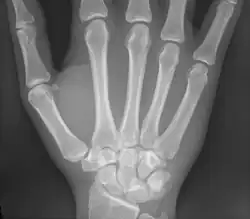

Les métacarpiens (ou os métacarpiens ou os du métacarpe) sont les os formant le métacarpe squelette de la paume de la main. Ils sont articulés dans leur partie supérieure[1] avec les os de la rangée distale du carpe et se prolonge au niveau de sa partie inférieure[1] par les phalanges proximales. Ces os sont unis par les muscles interosseux.

Les métacarpiens sont cinq petits os longs numérotés de 1 à 5, de dehors en dedans en position anatomique : 1 correspond au pouce et 5 à l'auriculaire. Chacun se compose d'une base proximale, d'un corps et d'une tête distale.